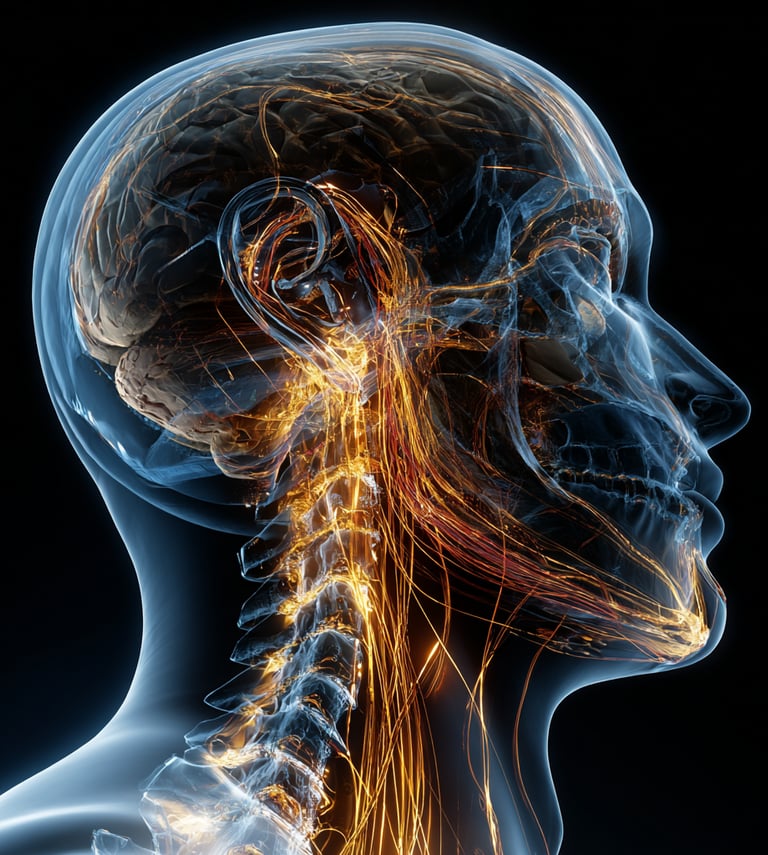

Encoded in our very design—within every breath, belief, motion, and cell lies the potential to awaken life’s fullest expression.

This is our collective birthright—the original biological framework, the emotional compass, the energetic rhythm. Human beings' living intelligence is activated daily. It is the truth embedded in every being on Earth. Precision Wellness Medicine is the system that returns us to ourselves.

AUDITORY PLASTICITY FRAMEWORK

Advance your understanding of how the brain adapts to sound. This framework translates cutting-edge neuroscience and ENT expertise into accessible practices that strengthen neural pathways, enhance focus, and restore cognitive harmony.

Harness the science of sound to support healing, balance, and resilience. Explore how sound frequencies interact with the body and mind, and discover practical approaches you can apply for everyday health and recovery.

NEURAL RESONANCE INTEGRATION FRAMEWORK